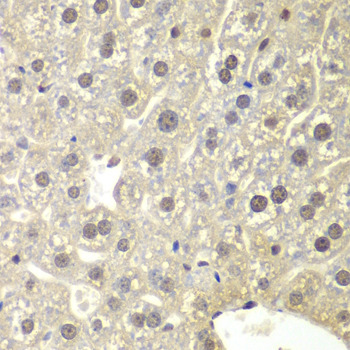

• A2164: image 2

Immunohistochemistry of paraffin-embedded mouse liver using NR3C1 antibody at dilution of 1:200 (400x lens).